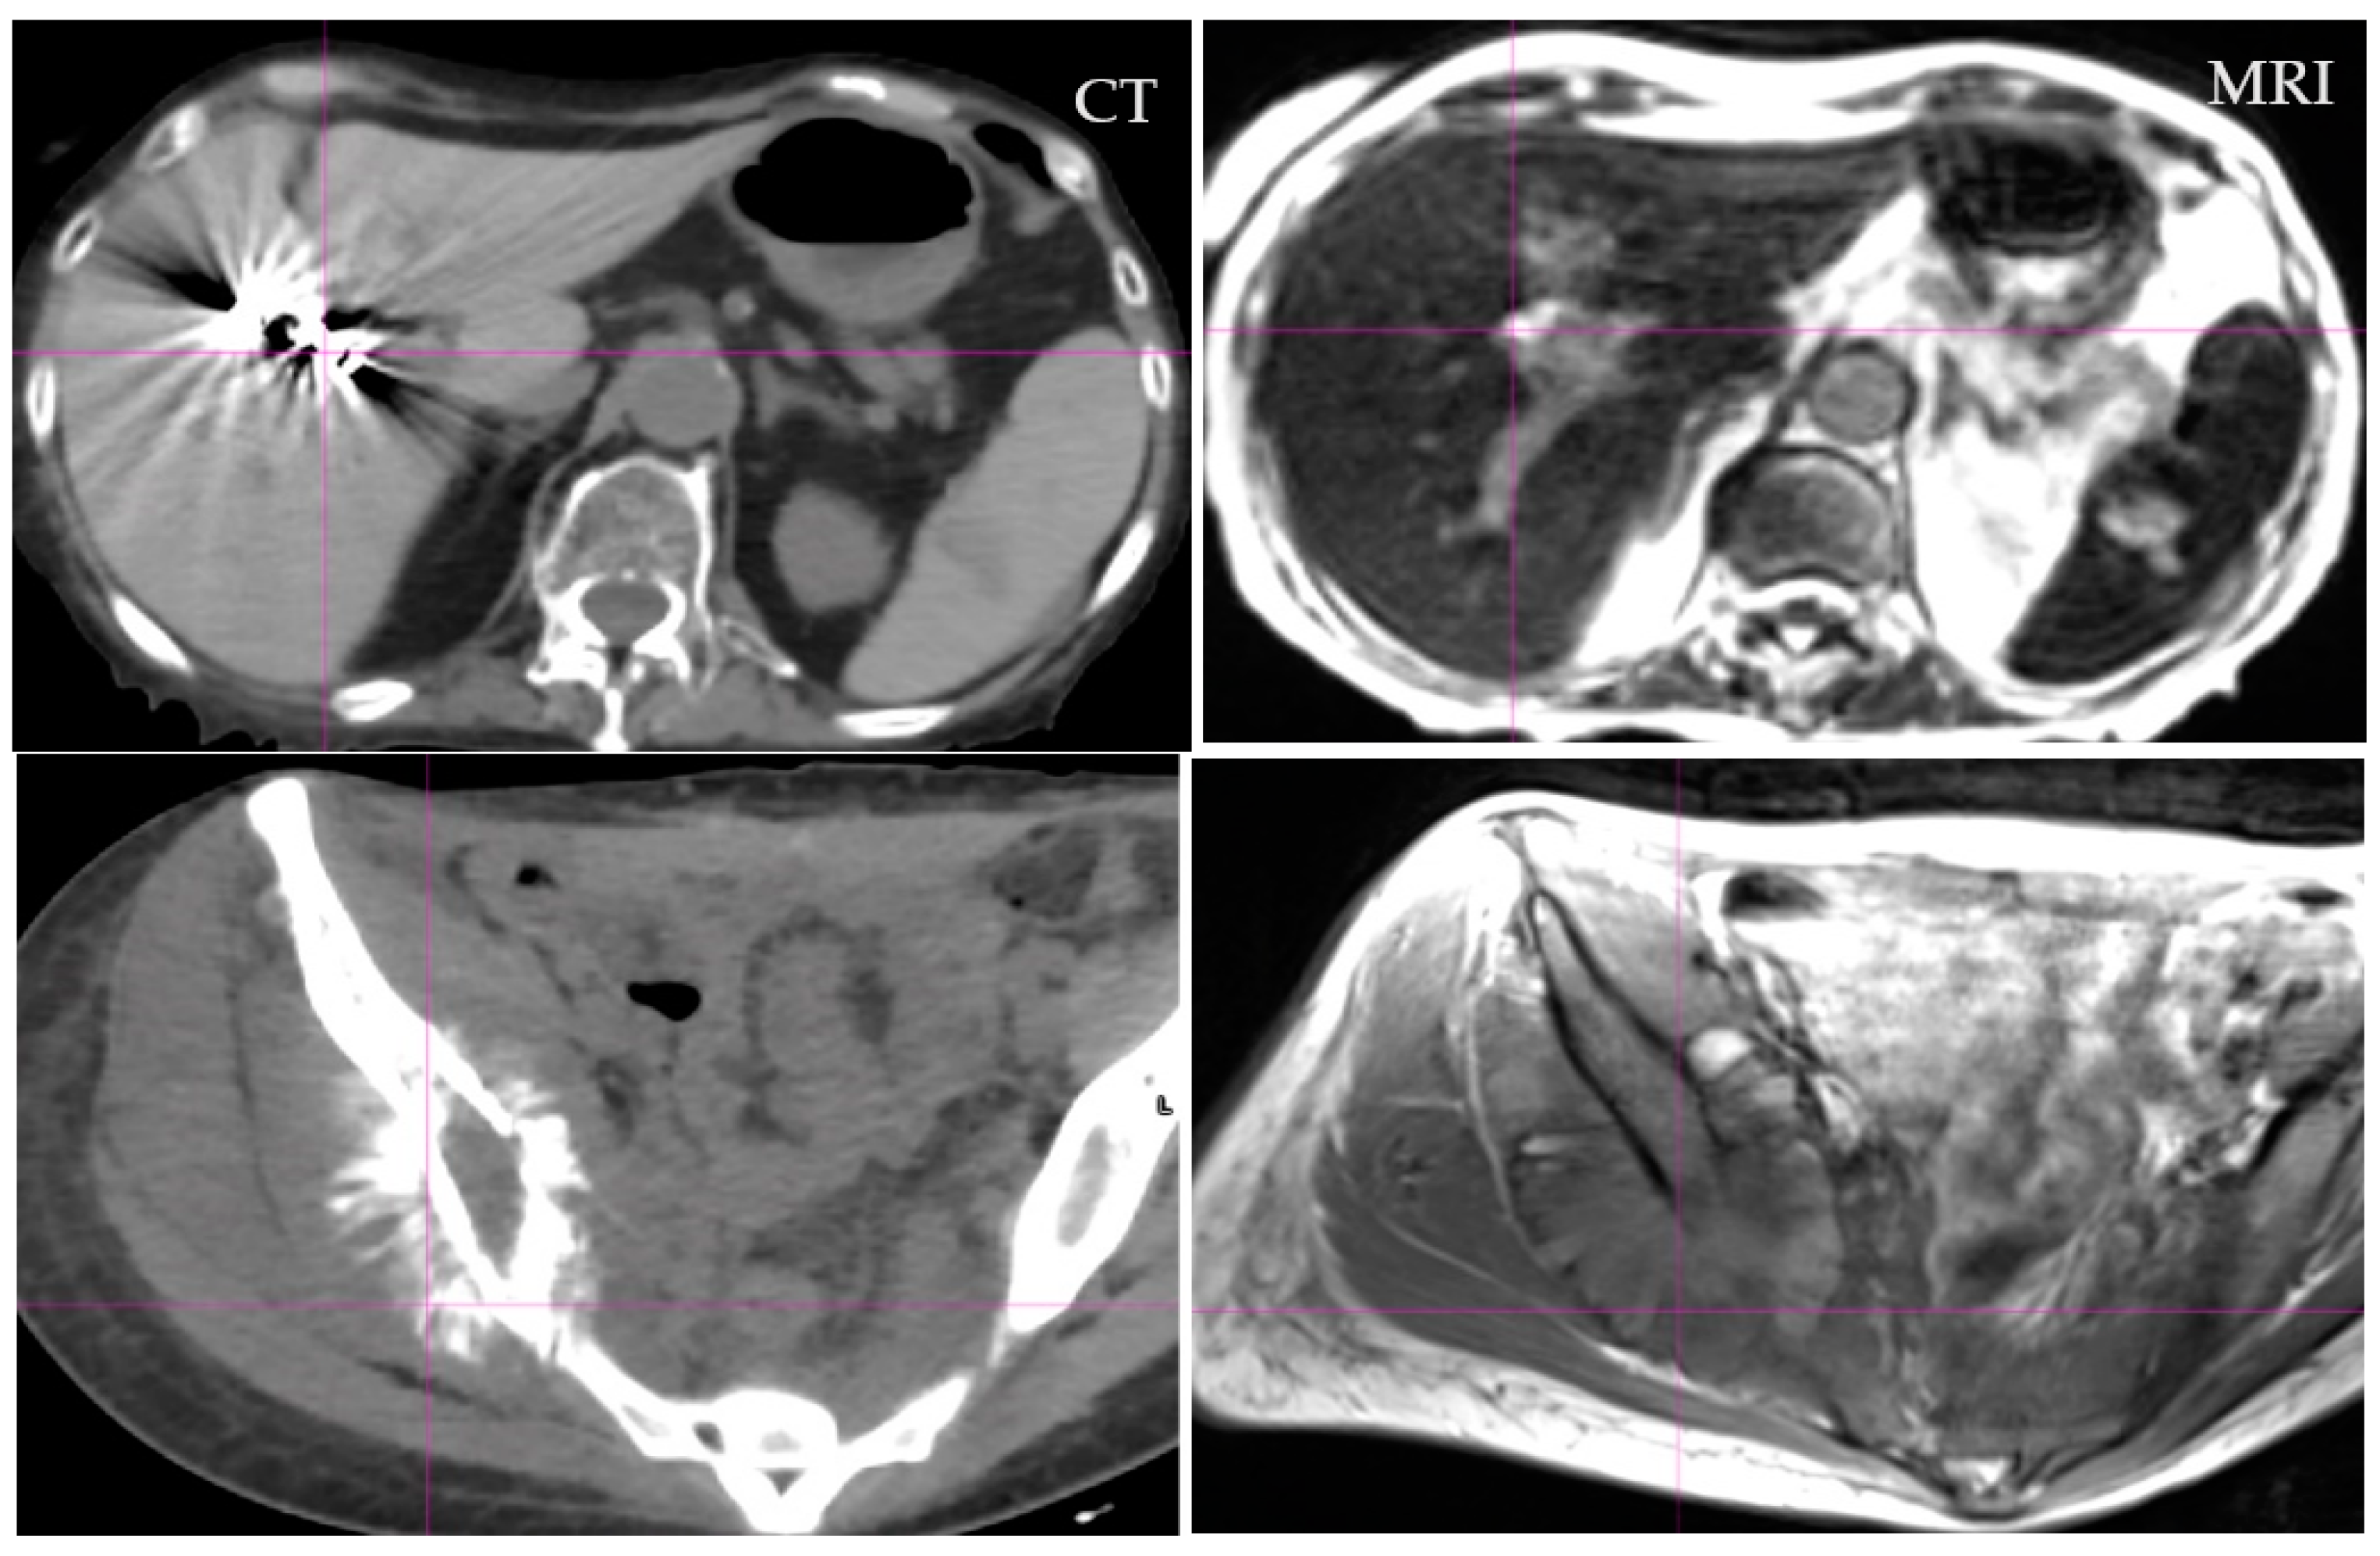

- Das, I.J.; McGee, K.P.; Tyagi, N.; Wang, H. Role and future of MRI in radiation oncology. Br. J. Radiol. 2019, 92, 20180505. [Google Scholar] [CrossRef]

- Chandarana, H.; Wang, H.; Tijssen, R.H.N.; Das, I.J. Emerging Role of MRI in Radiation Therapy. J. Magn. Reson. Imaging 2018, 48, 1468–1478. [Google Scholar] [CrossRef] [PubMed]